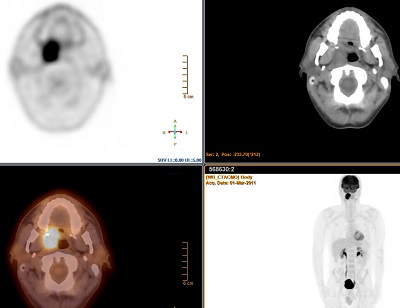

The NM Viewer application provides a powerful yet simple to use MI and multi-modality image review and analysis environment for clinical evaluation of MI planar, SPECT, SPECT/CT, PET/ CT, and PET/MR examinations. The application offers:

• MPR, MIP and fused 3D volume display

• 2D and 3D SUV measurements: SUV Body Weight, SUV Lean BodyMass, SUV Body Surface Area, and SUV Body Mass Index

• Automated 3D segmentation of lesions based on SUV value or percentage of SUV max, and the ability to export 3D contours in DICOMRT Structure Set format to radiation therapy planning systems